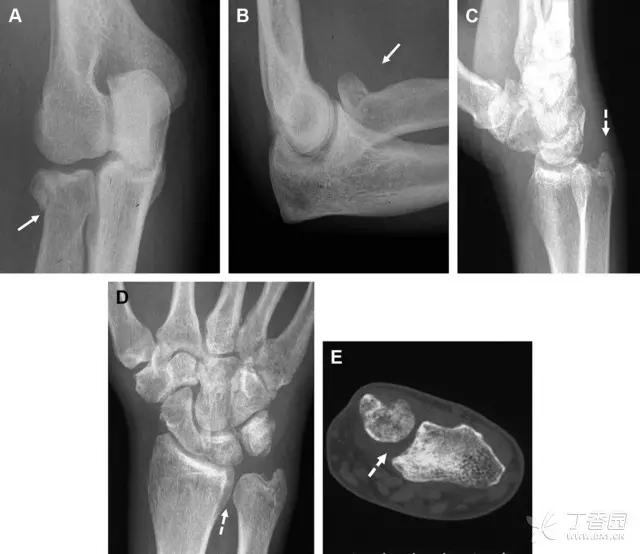

30 桡骨远端骨折

常规进行前后位、侧位、斜位 X 线检查,对于大多数桡骨远端骨折来说不容易漏诊;但是对于无移位的骨折,特别是桡骨茎突骨折,容易漏诊。桡骨茎突骨折是一斜行的骨折,常累及关节面,常发生于轴向应力或直接打击。

图 1 57 岁女性,摔倒后手掌撑地,桡骨茎突压痛。(A~C)前后位、斜位、侧位片示软组织肿胀(*)和发丝样骨折(白色箭头);(D~F)2 周后,前后位、斜位、侧位片示骨折线显明,由于新骨痂沉积而呈现透亮线与硬化线并存;(G~I)另一患者,桡骨茎突骨折在前后位及侧位片上显示不明显,而在斜位片显示更清楚

31 舟状骨骨折

舟状骨骨折 60%~70% 发生于腰部,15% 发生于近极, 10% 发生于远极, 8% 发生于远端关节面。除了常规的前后位、侧位、斜位片外,还需要拍专门的舟状骨位片(腕关节尺偏,以舟状骨为中心的腕关节前后位片),特别是鼻烟壶有压痛时。

图 2 舟状骨骨折 (A、B)第 1 例患者,舟状骨远极关节内骨折(白色箭头),斜位片显示较清楚(B);(C、D)第 2 例患者,舟状骨腰部骨折(虚线箭头),斜位片显示较清楚(D);(E~H)第 3 例患者,舟状骨近极骨折,常规 X 线片均未看到骨折,而在舟状骨位片上才能见到骨折(虚线圆)